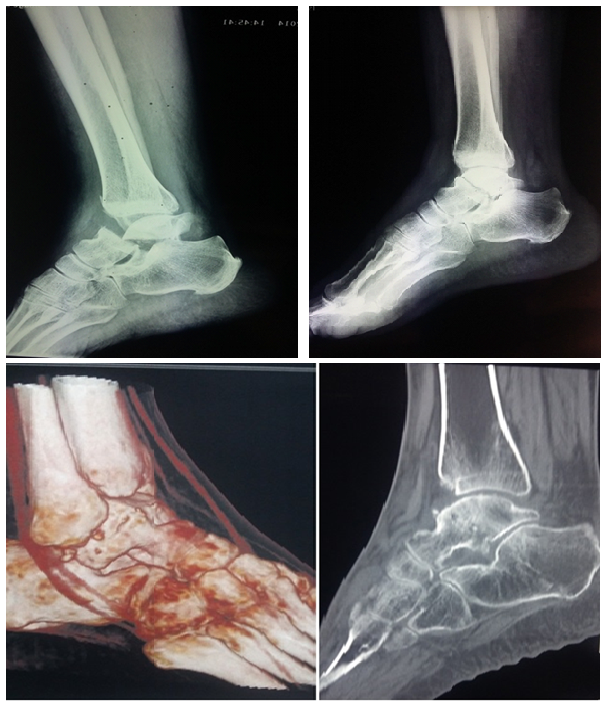

Place of Orthopedic Treatment in the Talus Fractures: About Two Cases

A. Elbahraouy, T. Elyaakoubi, A. Zaizi, S. Bouabid, M. Boussouga